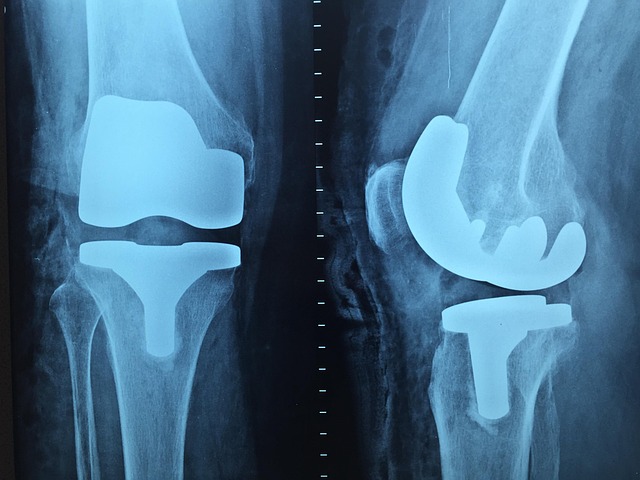

- 정기적으로 건강 검진을 받아 고관절 상태를 확인하세요. 특히 고령층이나 관절염 가족력이 있는 경우에는 더욱 주의가 필요합니다.

정기 검진은 미리 문제를 발견하고 예방하는 데 효과적입니다.